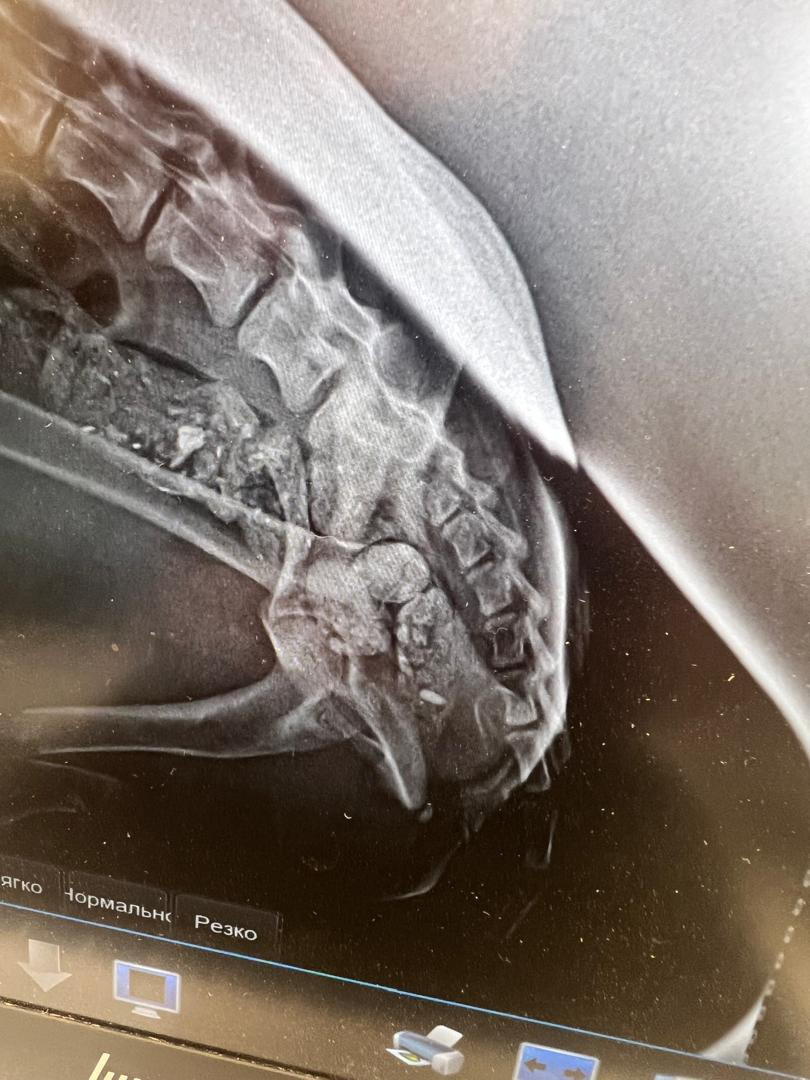

Ош мамлекеттик университетинин ветеринардык клиникасынын дарыгерлери алгачкы жолу иттин эки арткы бутунун сынуусун остеосинтез ыкмасы менен ийгиликтүү дарылоону ишке ашырышты.

Остеосинтез – бул сынган сөөктөрдү атайын металл пластиналар жана бурамалардын жардамында хирургиялык жол менен бекитүү ыкмасы болуп, ал сөөктүн туура жана бат айыгышын камсыздайт.

Операциянын жаныбардын эки арткы бутуна тең остеосинтез жүргүзүлгөнү менен өзгөчөлөнөт. Бул болсо жогорку деңгээлдеги кесипкөйлүктү, заманбап хирургиялык шаймандарды жана абсолюттук стерилдүүлүктү талап кылган татаал жараян.

Хирургиялык топ операциянын жүрүшүндө сынган сөөктөрдү так анатомиялык абалга келтирип, атайын металл пластиналар менен бекитишкен. Мындай ыкма гипс же шина коюу сыяктуу салттуу дарылоо ыкмаларына караганда реабилитациялык мөөнөттү кыйла кыскартат. Операциядан кийин клиниканын стационардык бөлүмүндө дарыгерлердин көзөмөлүндө болуп, абалы тыкыр байкоодо болду. Азыркы тапта абалы туруктуу деп бааланууда.